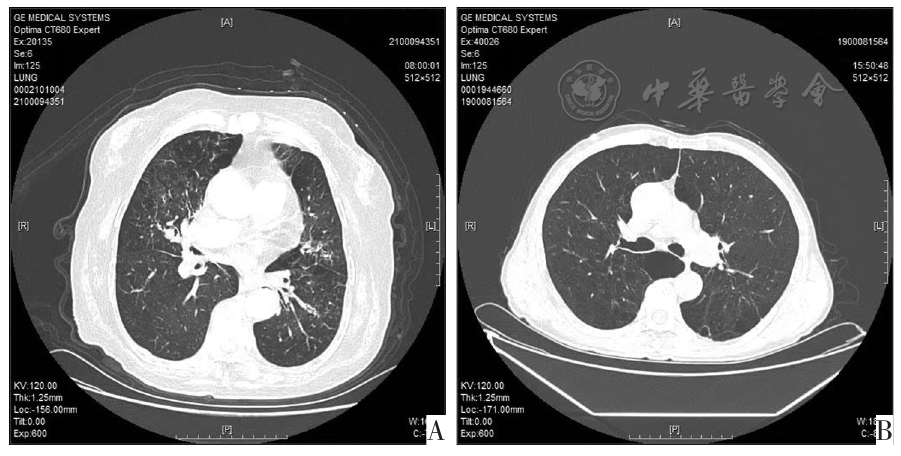

图1 COPD伴肺气肿患者典型CT图像。图A为EOS型COPD伴肺气肿患者CT图,大片透亮区,肺小叶破坏严重,呈低密度、无壁、不规则状;图B为非EOS型COPD伴肺气肿患者CT图,小叶中央型气肿区域较小,呈斑片状,肺纹理和小血管数量减少